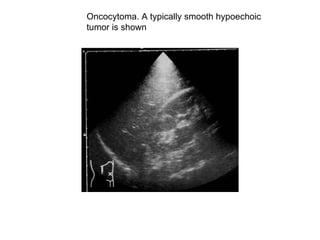

Oncocytoma. A typically smooth hypoechoic  tumor is shown